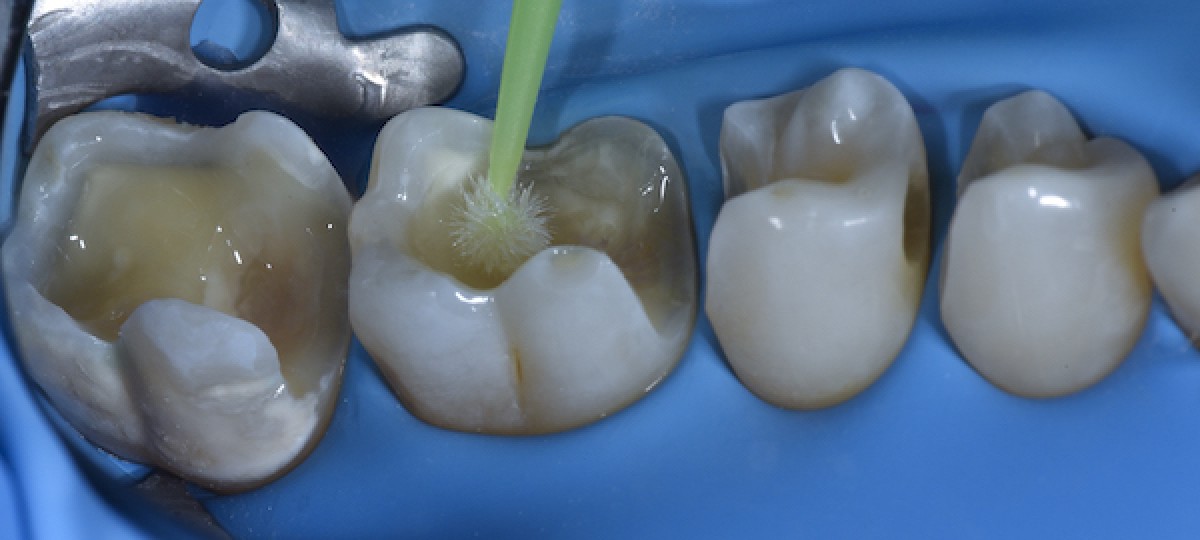

Universal adhesive system applied in self-etch mode (Fig.8)